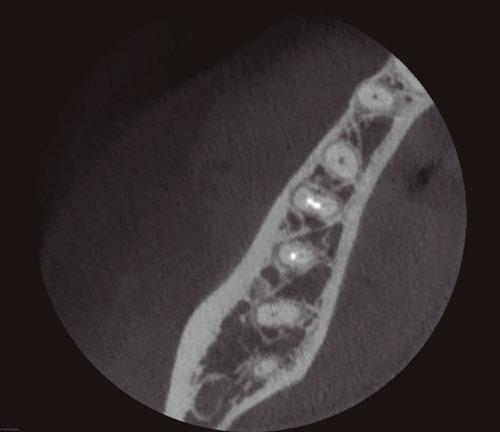

5A-5B: CBCT was taken during initial endodontic exam in 2023. 5A. Coronal CBCT

revealed a 6.1 mm x 3.0 mm hypodensity extending from the apical and distal aspect of No. 11. 5B. Sagittal

slices revealed the presence of bone between tooth No. 11 and implant No. 12

spacing of 3.4 mm between the two was noted (Figure 4). The recommended amount of space between a natural tooth and dental implant should be 1.5 mm-2 mm, proving adequate spacing in this case.15 Coronal views of the CBCT evaluation revealed a 6.1 mm x 3.0 mm hypodensity extending from the apical and distal aspect of tooth No. 11 (Figure 5A). Sagittal slices revealed the presence of healthy bone morphology between the distal border of the hypodensity on tooth No. 11 and implant No. 12, thus the hypodensity did not extend to the implant (Figure 5B). Reference was made to the Treatment Options for the Compromised Tooth: A Decision Guide published by the AAE in 2017 to determine prognosis.16 In evaluating the coronal tooth structure, tooth No. 11 had a well-fitting crown with adequate margins, no need for crown lengthening, and required only routine endodontic treatment placing it in the favorable category. The periodontal condition of tooth No. 11 was also favorable with probing depths equal to or less than 3 mm and a normal periodontium. Lastly, the apical periodontitis was expected to resolve following non-surgical root canal treatment.16 Thus, tooth No. 11 was diagnosed as pulpal necrosis with asymptomatic apical periodontitis with a favorable prognosis. Nonsurgical root canal treatment was planned, and informed consent was obtained.

Figure 4: Sagittal CBCT slice revealed 3.4 mm of space between the apex of tooth No. 11 and the mesial border of implant No. 12